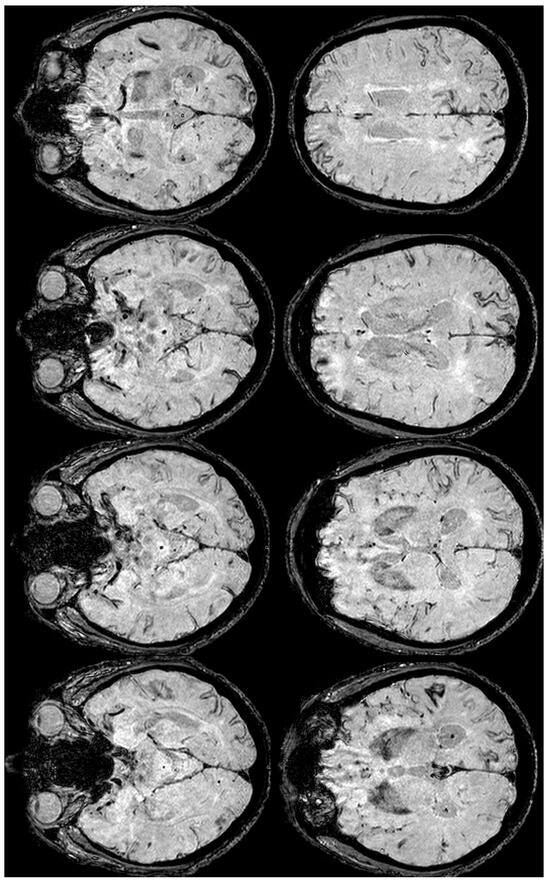

2. December 2013: Sulcal SAH and TFNEs

6. December 2017: Recurrent SAH